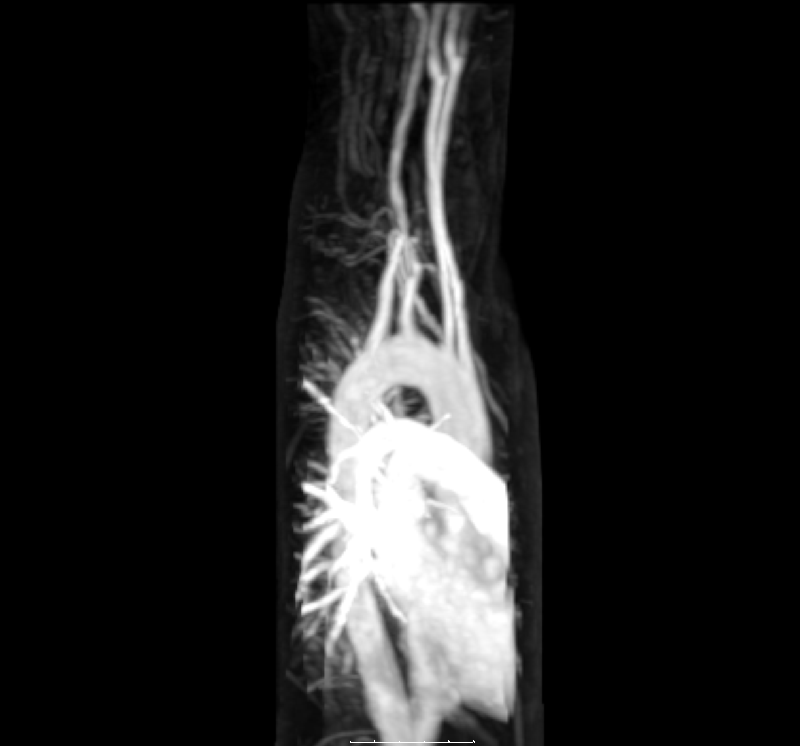

다른 침습적인 방법도 사용할 수 있다. 동맥에 삽입된 캐뉼라 또는 카테터를 사용하여 맥압 또는 폐쐐기압을 측정할 수 있다. 동맥 나무를 시각화하기 위해 동맥에 염료를 주입하는 혈관 조영술은 심장(관상 동맥 조영술) 또는 뇌에서 사용할 수 있다. 동맥을 시각화하는 동시에 스텐트를 삽입하여 막힘이나 협착을 해결하고, 코일을 삽입하여 활성 출혈을 관리할 수 있다. MRI를 사용하여 동맥을 영상화할 수 있으며, 이를 MRI 혈관 조영술이라고 한다. 폐로의 혈액 공급을 평가하기 위해 CT 폐 혈관 조영술을 사용할 수 있다. 혈관 초음파는 정맥계와 동맥계에 영향을 미치는 혈관 질환을 조사하는 데 사용될 수 있으며, 협착, 혈전증 또는 정맥 부전의 진단을 포함한다. 카테터를 사용하는 혈관 내 초음파도 가능하다.